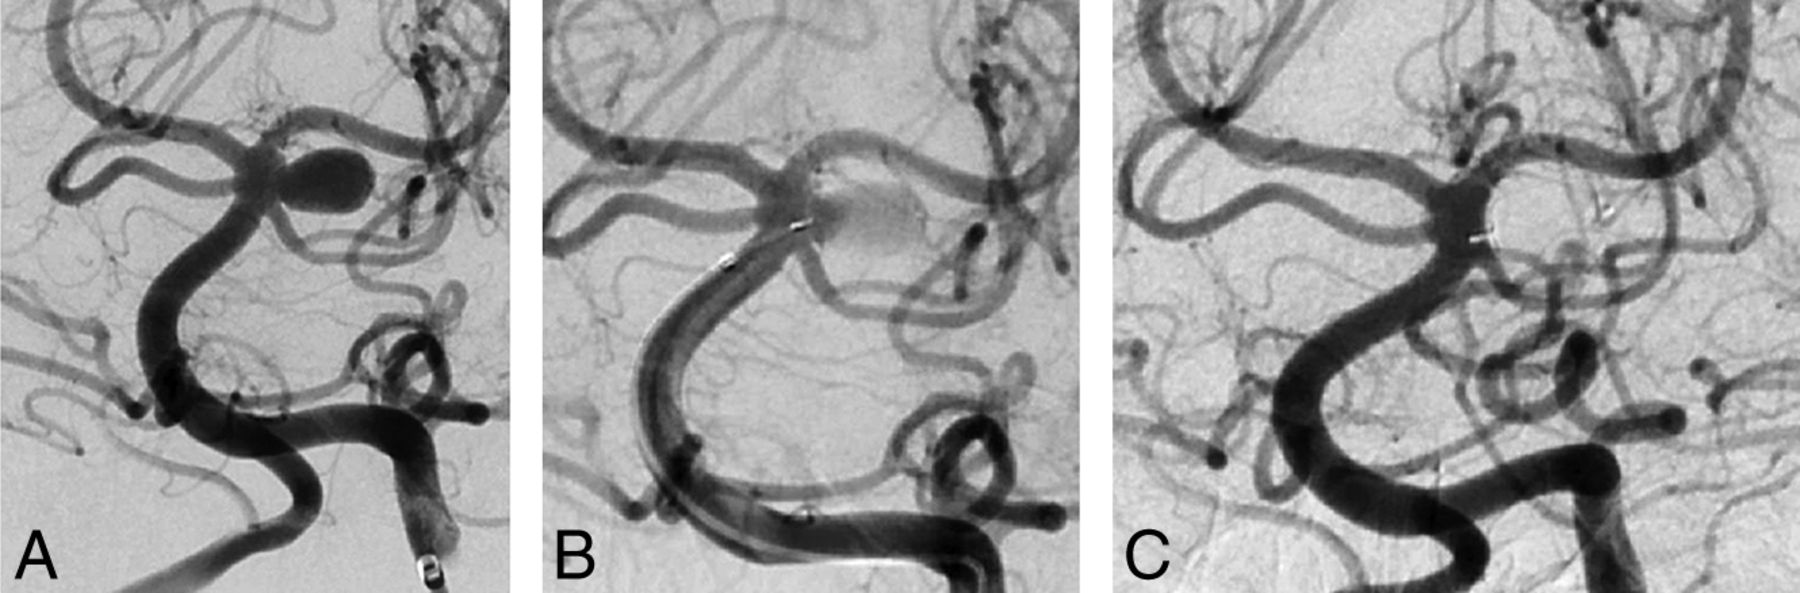

The procedure was completed with a WEB device only as intended in 83 (81.4%) aneurysms (Fig 1), whereas in 7 (6.9%), additional coils were necessary to completely fill the aneurysm. In another 8 (7.8%) procedures, a self-expanding stent was implanted to guarantee a stable position of the WEB. This was combined with additional coiling in 1 aneurysm.

A first follow-up angiography was available for 78/98 (79.6%) aneurysms to date after a median of 3.5 months (range, 1.0–21.0 months), showing complete occlusion (grades 1 and 2) in 47/78 (60.2%) and sufficient aneurysm occlusion (grades 1–3) in 63/78 (80.7%). Of the remaining 20 patients, 9 died as consequence of their SAH, 9 were lost to follow-up, 1 died of causes unrelated to the treated aneurysm, and 1 died of causes related to the procedure (see below). A second follow-up angiography was performed in 49/98 (50.0%) after a median of 8.6 months (range, 2.0–20.0 months), showing complete occlusion in 29/49 (59.2%) and sufficient occlusion in 38/49 aneurysms (77.6%). Retreatment has been necessary in 10 aneurysms to date due to a regrowth of the aneurysms or a clustering of the WEB.

At least 1 follow-up angiography was performed in 91.8% (56/61) of all unruptured aneurysms, showing complete occlusion in 60.8% (34/56) and sufficient occlusion in 82.2% (46/56). Thirty-seven of the 61 aneurysms (60.7%) were evaluated in a second angiography to date. Of those, 59.4% (22/37) were completely occluded and 78.3% (29/37) showed sufficient occlusion.